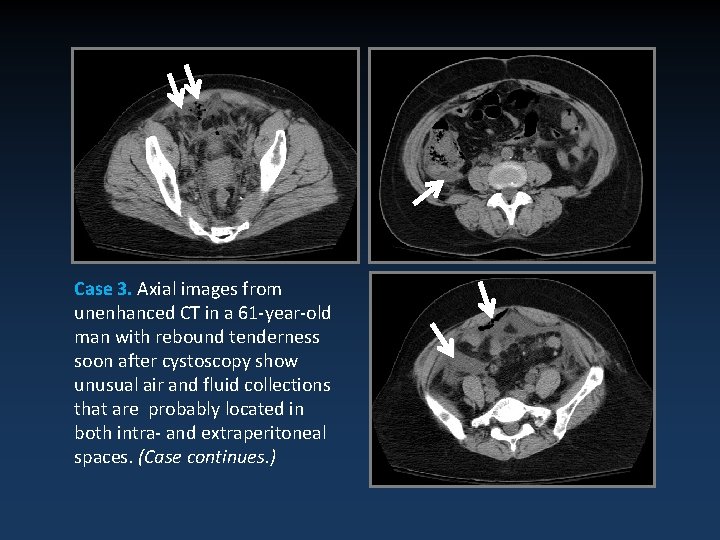

Case 3. Axial images from unenhanced CT in a 61 -year-old man with rebound tenderness soon after cystoscopy show unusual air and fluid collections that are probably located in both intra- and extraperitoneal spaces. (Case continues. )